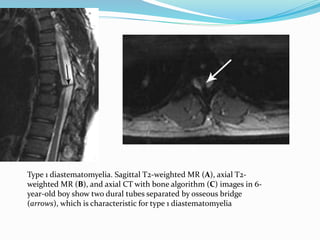

Type 1 diastematomyelia. Sagittal T2-weighted MR (A), axial T2-

weighted MR (B), and axial CT with bone algorithm (C) images in 6-

year-old boy show two dural tubes separated by osseous bridge

(arrows), which is characteristic for type 1 diastematomyelia